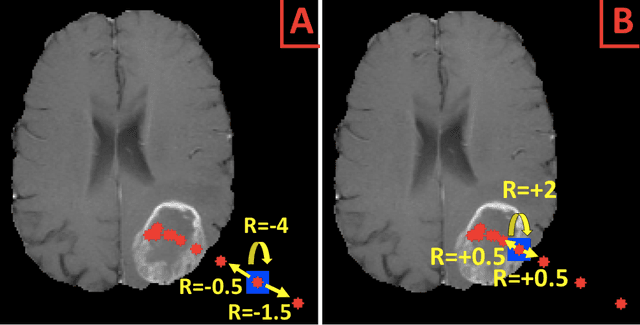

Abstract:Purpose: AI in radiology is hindered chiefly by: 1) Requiring large annotated data sets. 2) Non-generalizability that limits deployment to new scanners / institutions. And 3) Inadequate explainability and interpretability. We believe that reinforcement learning can address all three shortcomings, with robust and intuitive algorithms trainable on small datasets. To the best of our knowledge, reinforcement learning has not been directly applied to computer vision tasks for radiological images. In this proof-of-principle work, we train a deep reinforcement learning network to predict brain tumor location. Materials and Methods: Using the BraTS brain tumor imaging database, we trained a deep Q network on 70 post-contrast T1-weighted 2D image slices. We did so in concert with image exploration, with rewards and punishments designed to localize lesions. To compare with supervised deep learning, we trained a keypoint detection convolutional neural network on the same 70 images. We applied both approaches to a separate 30 image testing set. Results: Reinforcement learning predictions consistently improved during training, whereas those of supervised deep learning quickly diverged. Reinforcement learning predicted testing set lesion locations with 85% accuracy, compared to roughly 7% accuracy for the supervised deep network. Conclusion: Reinforcement learning predicted lesions with high accuracy, which is unprecedented for such a small training set. We believe that reinforcement learning can propel radiology AI well past the inherent limitations of supervised deep learning, with more clinician-driven research and finally toward true clinical applicability.